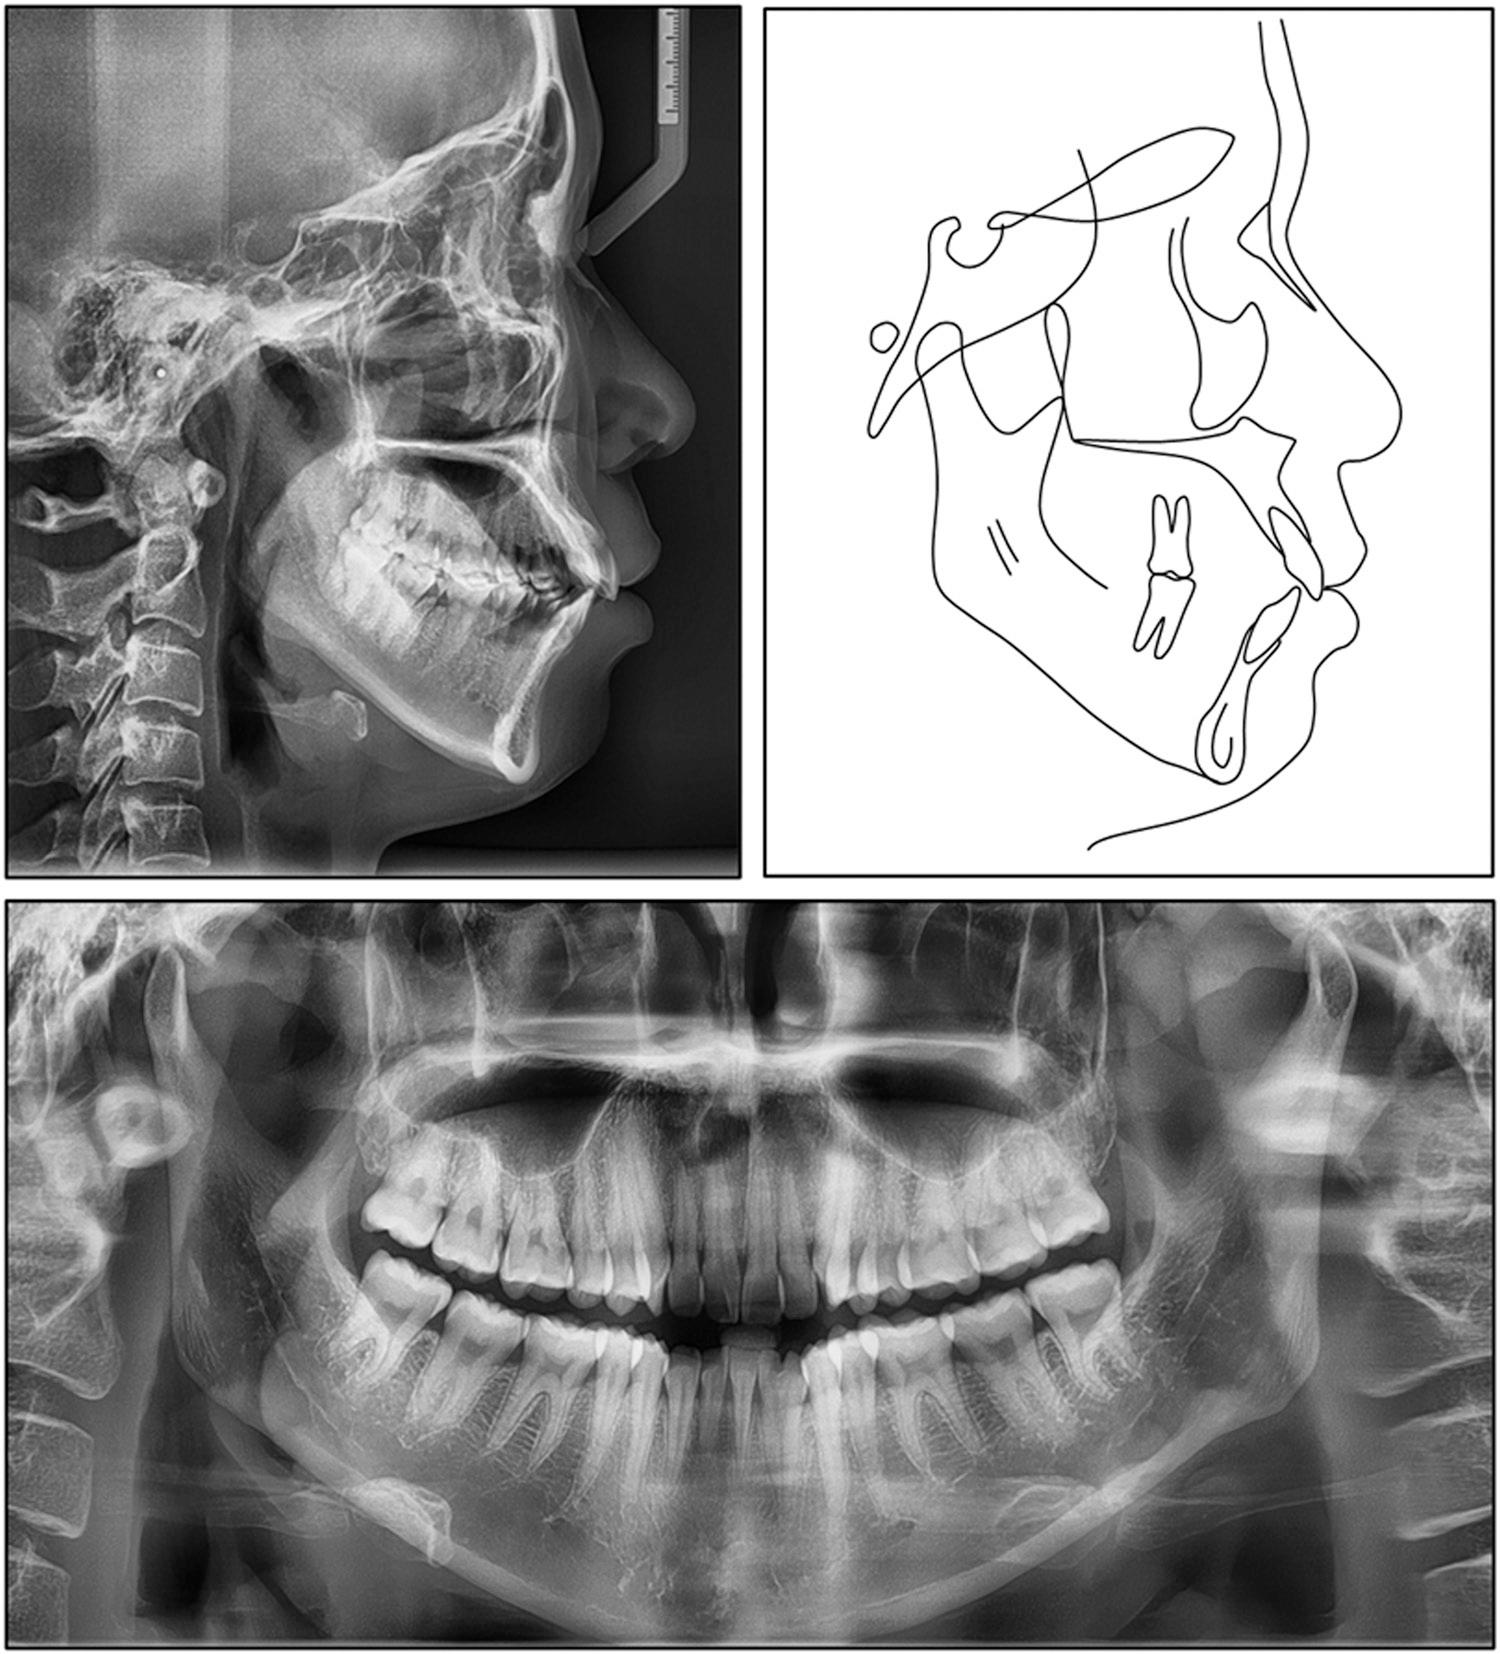

A pretreatment panoramic radiograph confirmed the presence of 30 permanent teeth with normal alveolar bone levels (Figure 3). On the left side, the fused mandibular lateral incisor-canine complex displayed two separate pulp chambers converging into a single root canal, whereas on the right, the corresponding fused tooth exhibited a single pulp chamber and a single root canal.

Pretreatment lateral cephalogram, panoramic radiograph, and tracing.

The lateral cephalogram showed a mild skeletal Class II pattern (SNA, 83.5°; SNB, 79.2°; ANB, 4.4°) with a vertical growth tendency (FMA, 33.9°; Björk sum, 402.5°; gonial angle, 129.1°) (Table I). The sagittal jaw disharmony was minimal (Wits appraisal, -0.2 mm; Pog-to-N perpendicular, -4.5 mm), and the maxilla was positioned slightly anterior to the cranial base (A-N perpendicular, +2.2 mm). The maxillary incisors were proclined and prominent (U1-SN, 106.9°; U1-NA, 23.3°, 7.0 mm), while the mandibular incisors were normally inclined (IMPA, 89.9°; L1-NB, 31.5°, 9.3 mm), generating an interincisal angle of 120.8°. The occlusal plane was steep (cant 8.5°). The overjet was 4.2 mm and overbite 2.6 mm. A soft-tissue analysis confirmed a slightly convex profile with the upper and lower lips 1.4 mm and 2.3 mm, respectively, anterior to the E-plane, while the nasolabial angle measured 86.5°.